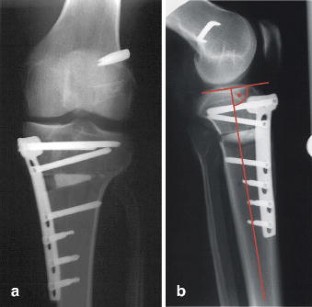

Fig. 3a, b.